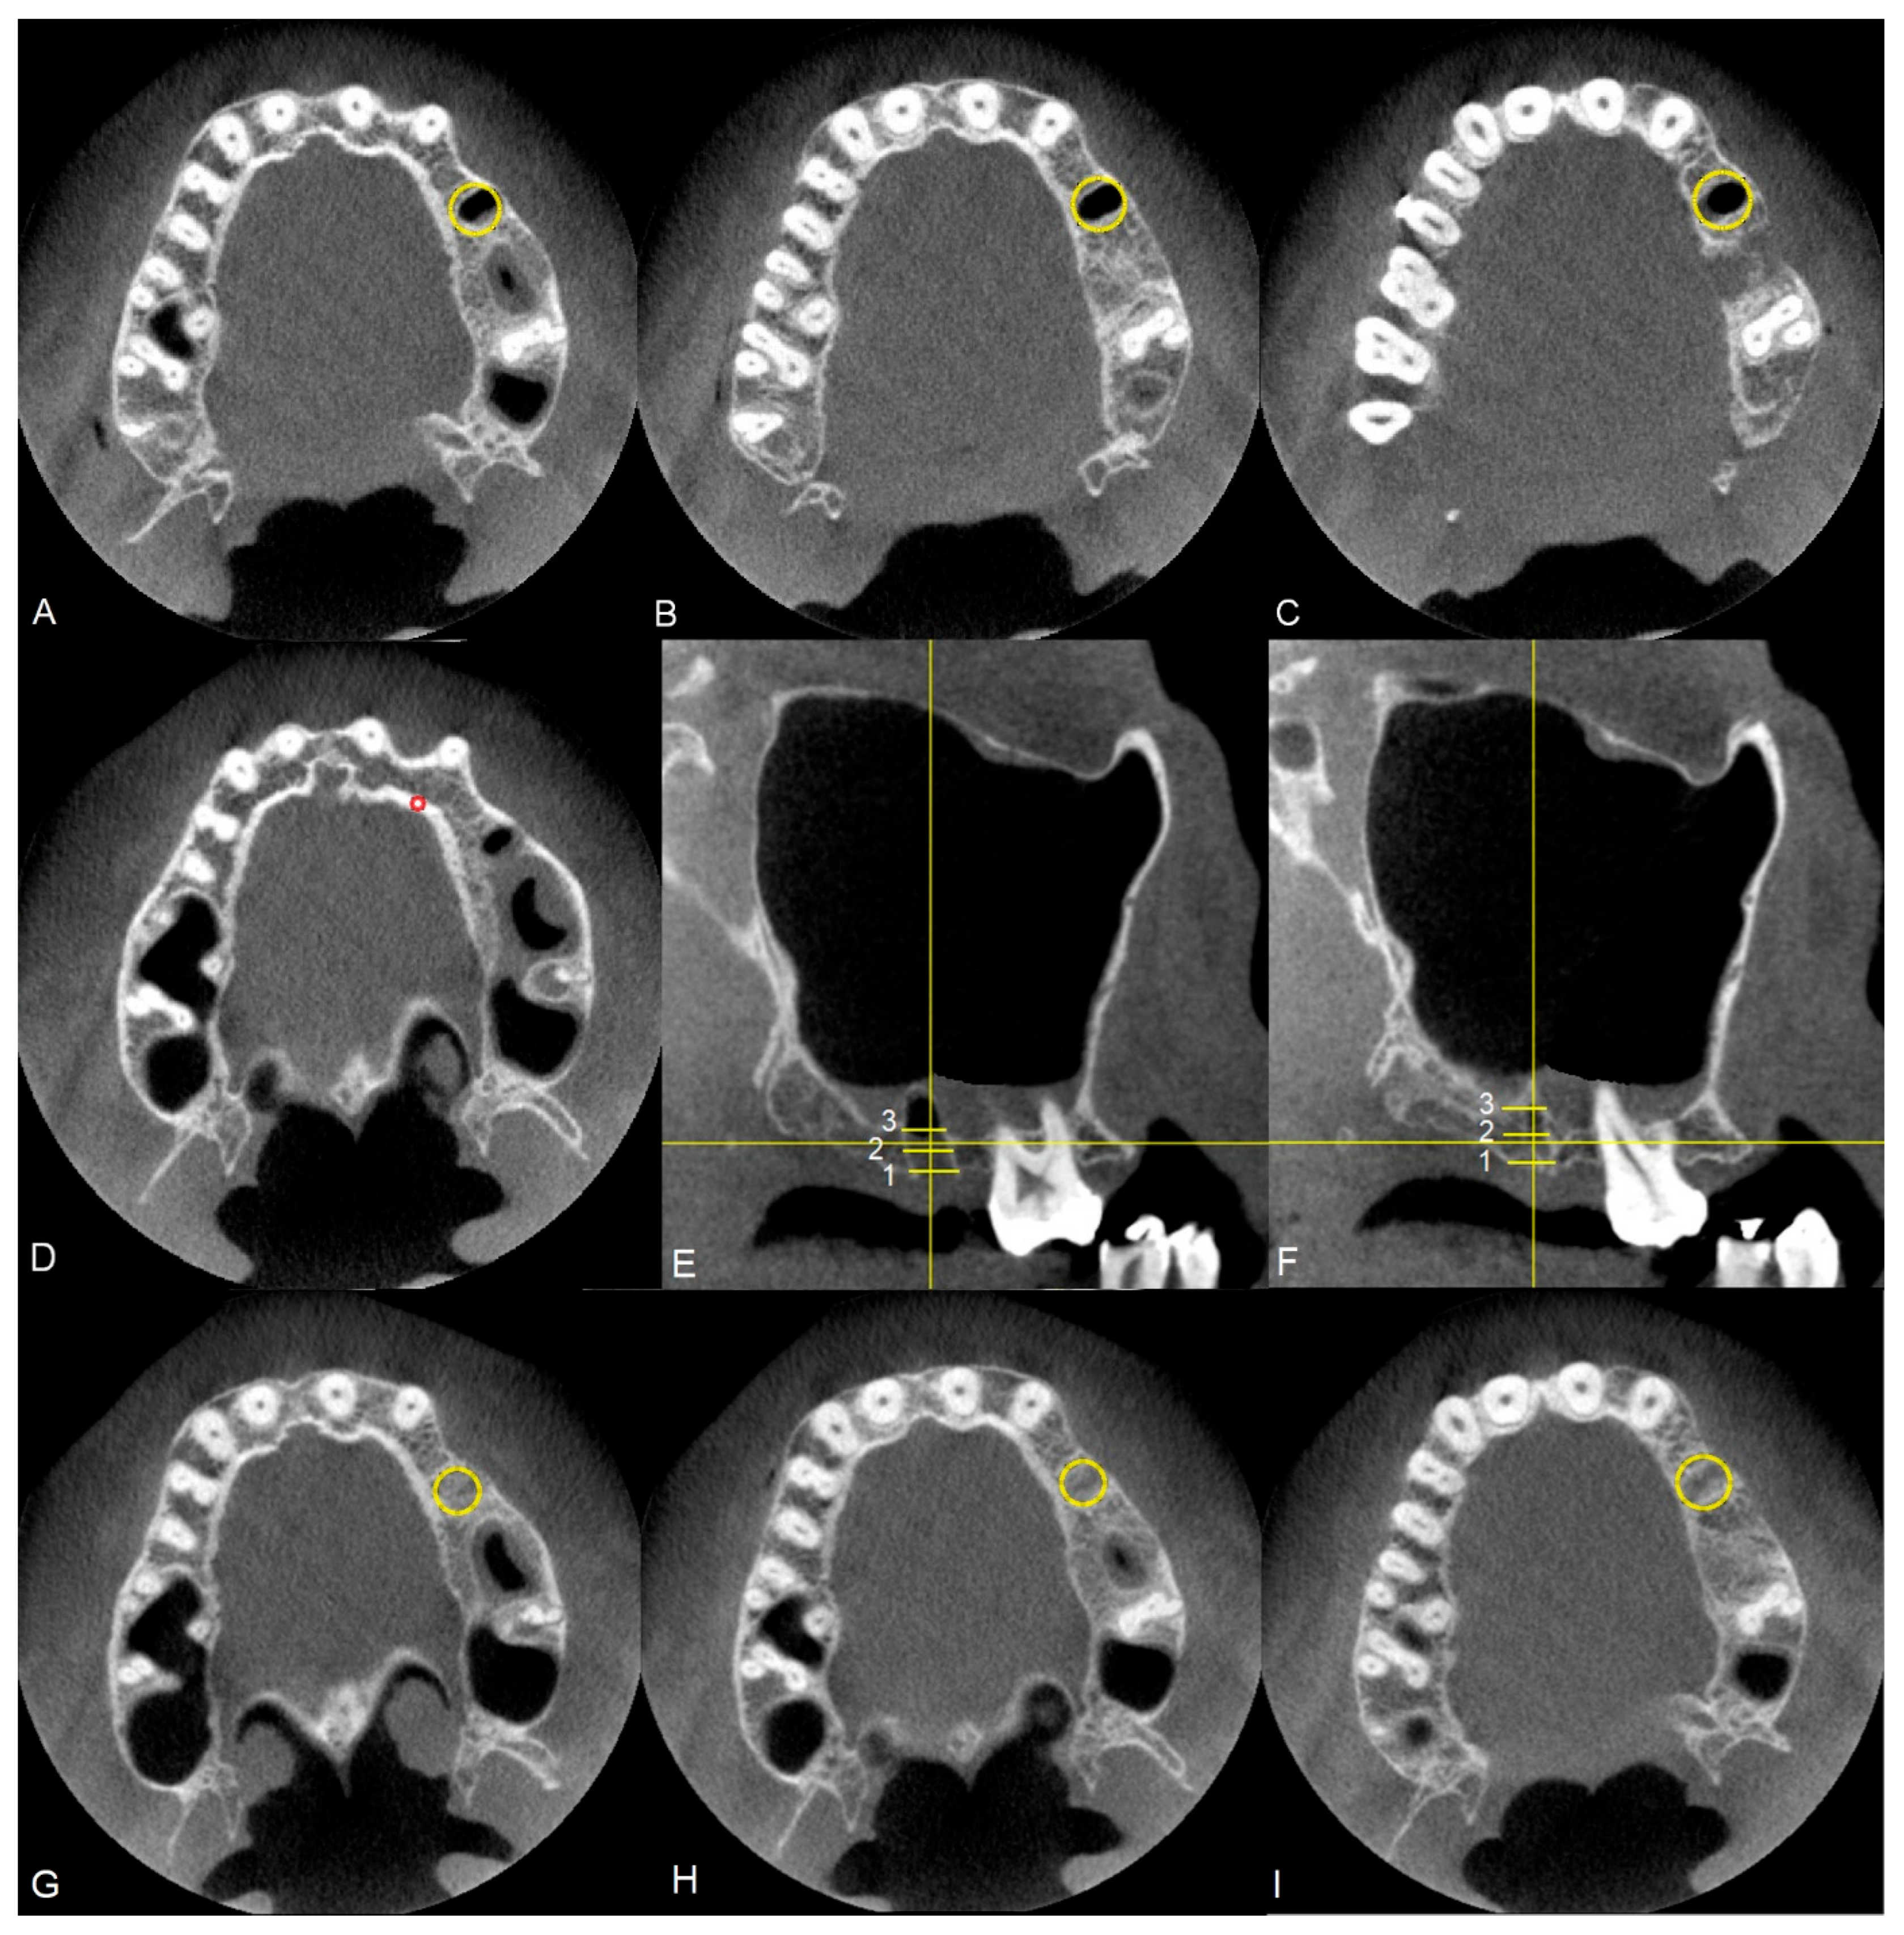

Measurements of bone tissue density and surrounding tissues were performed on images obtained from CBCT scans, appropriately for patients treated using a membrane and the Rehrmann method, in accordance with the methodology shown in Figure 6. Each time, an area (ROI—region of interest) was marked where average densities in Hounsfield units were collected at three different heights of the alveolar process, specifically near the sinus, in the middle of the alveolus, and at the level of the neck of the extracted tooth. Density measurements were also performed to normalize the density of the participant’s bone tissue (Figure 6A–D). It was decided that the obtained tissue density measurements would be referenced to the density of compact bone tissue to reduce the influence of individual variability within the test group. The value was directly calculated as the ratio of the mean density at the site of tooth extraction to the mean density of compact bone tissue. All measurements were performed on cross-sectional slices, with layer selection based on simultaneous control of the position relative to sagittal sections (Figure 6E). Measurements were taken for each group immediately after tooth extraction (Figure 6A–E) and after 90 days of observation (Figure 6F–H). From the densities calculated at the three heights, the arithmetic mean was determined and included in the statistical analyses.

Figure 6. CBCT. Methodology for selecting cross-sections for density measurements in the transverse plane, where (A) measurement at the socket, (B) measurement in the center of the alveolus, (C) measurement at the level of the neck of the extracted tooth, (D) density measurement for normalizing the bone density of the respective volunteer, (E) schematic representation of measurement sites on the sagittal section on day 0, (F) schematic representation of measurement sites on the sagittal section after 90 days, (G) measurement at the socket performed after 90 days, (H) measurement in the center of the alveolus performed after 90 days, (I) measurement at the level of the neck of the extracted tooth performed after 90 days. The measurement of the reference value of bone tissue density after 90 days from the procedure was carried out in the same manner as the measurements immediately after tooth extraction.